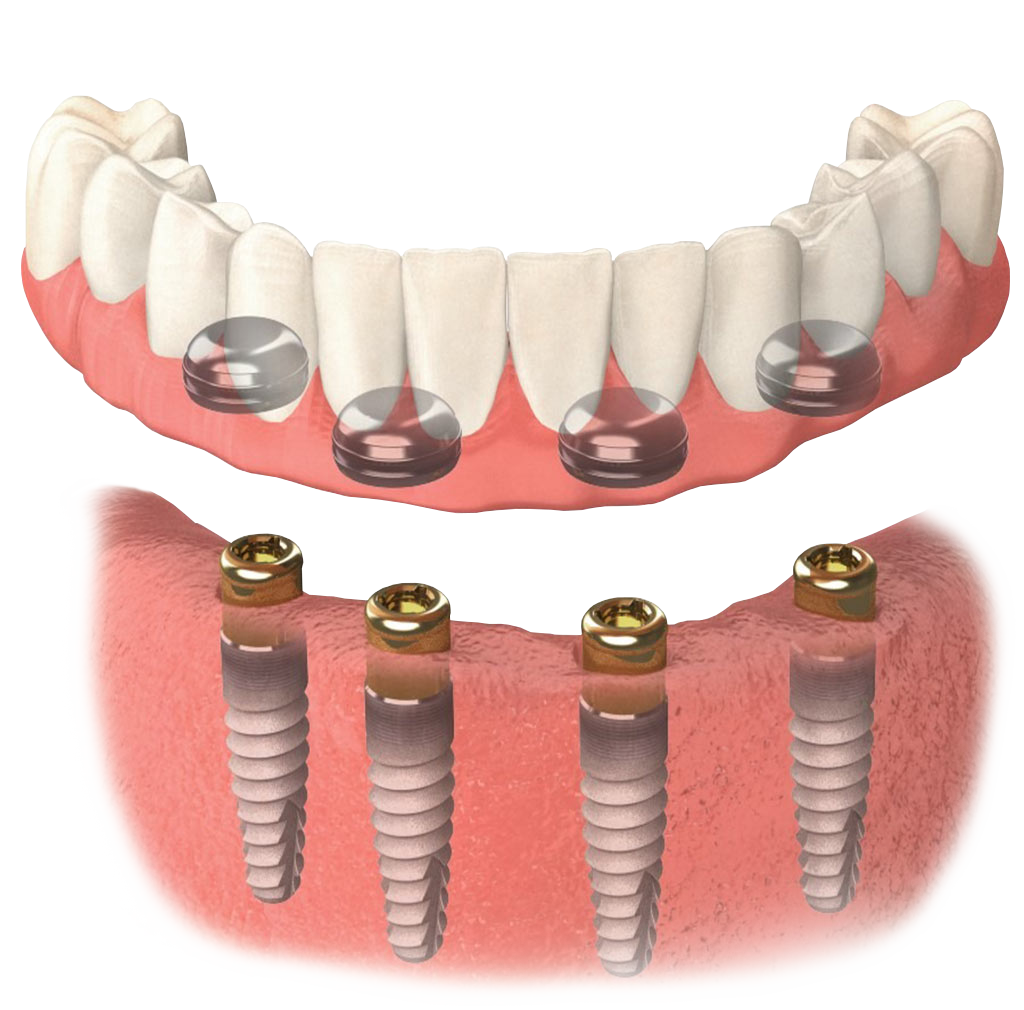

Современная стоматология: Железные зубные импланты